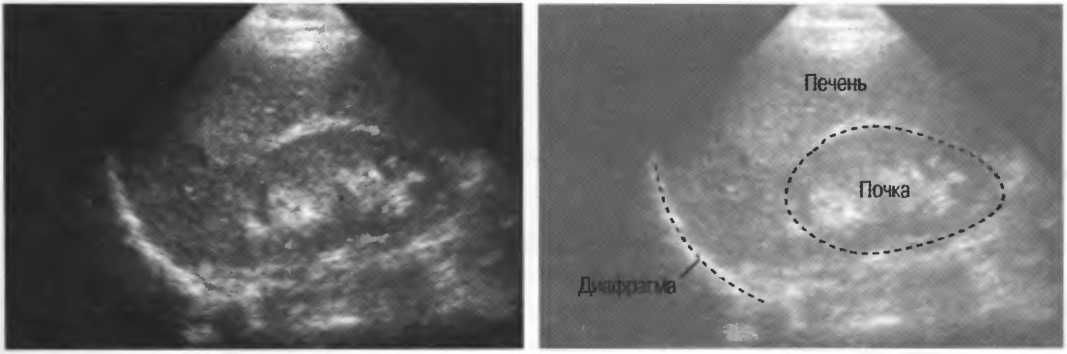

4. У здоровых обследуемых паренхима печени должна быть немного более эхогенна. чем кора рядом расположенной почки (рис. 26).

Рис.26. Продольный срез через печень и правую почку: нормальная паренхима печени более эхогенна, чем паренхима нормальной почки. Это еще один способ проверки качества изображения.